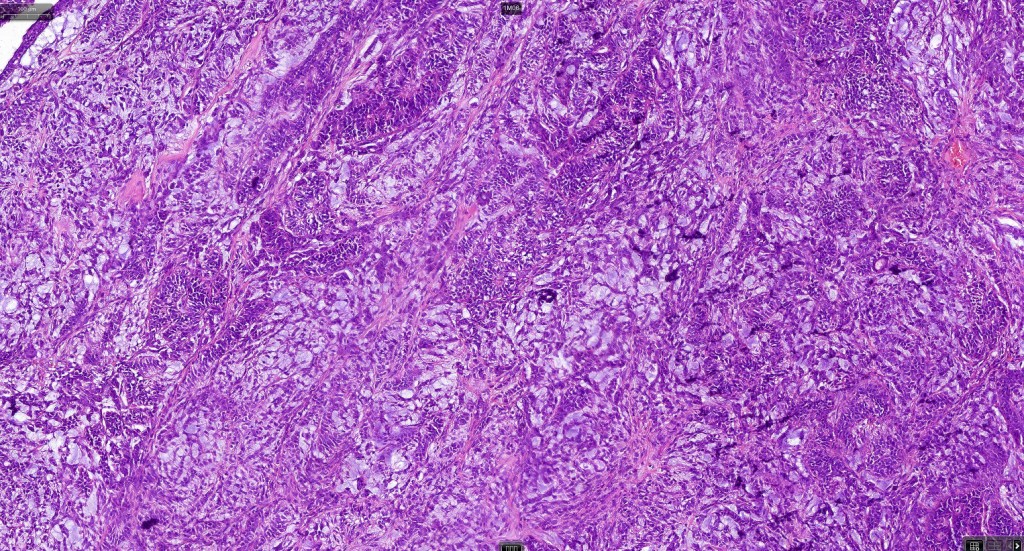

Histological features

•Pure population of myoepithelial cells dispersed in sheet-like, reticular, whorled or fascicular patterns in a myxoid or hyaline stroma

•Cell types include epithelioid, spindled, histiocytoid & plasmacytoid

•Syncytial myoepithelioma characterized by sheet-like growth of ovoid to spindle cells with pale cytoplasm, syncytial borders & vesicular nuclei

•In malignant myoepithelioma there is an infiltrating border, marked pleomorphism, high mitotic rate & necrosis. Perineural infiltration & lymphovascular invasion may be seen